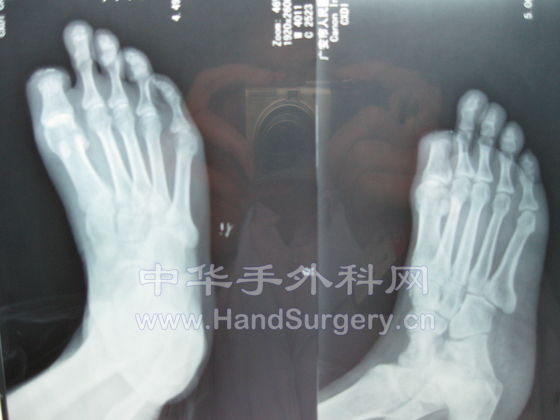

[其他] 动脉闭塞性脉管炎一例!~请前辈们指示!~

IMG_0115.jpg IMG_0116.jpg IMG_0117.jpg IMG_0118.jpg IMG_0119.jpg IMG_0120.jpg IMG_0121.jpg IMG_0122.jpg

患者于两年前无明原因出现右足麻木,疼痛,未经治疗!

于去年2008年12月份右足拇指甲沟炎,在外院行截指术后创面不愈合至今.

在外院以骨髓炎为诊断治疗至今.

下肢抬高(Buerger)试验阳性

足背动脉及胫后动脉未触及.